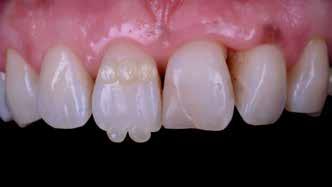

A héjak átadását követően kialakuló állapot valósághű módon történő bemutatása érdekében próbapasztát alkalmaztunk (Try-In-Paste; Variolink® Esthetik Try-In-Paste, Ivoclar Vivadent) (11. ábra). A próba során ellenőrizzük a héjak színét, formáját és transzparenciáját. A próbapaszta alkalmazásának egyik lényeges pontja, hogy a paszta színe egyezzen meg a végleges beragasztás során alkalmazni kíván ragasztóanyag színével. A héjak végleges rögzítése során mindig adhezív rendszereket használunk.

A preparálást nem igénylő héjak általában nagyon vékonyak, és sajnálatos módon ebből adódóan a végleges átadásuk előtt történő előkészítés során könnyen eltörhetnek. Csupán a páciensek saját fogain történő végleges rögzítés révén kapják meg azt az alátámasztottságot, amely a végleges töréssel szembeni ellenálló képességüket biztosítja. A fogpróba során a héjakat egyesével a fogakra helyezzük, és ellenőrizzük a pontos illeszkedésüket, valamint az approximális kontaktpontok megfelelőségét. Amenynyiben mindent rendben találtunk, úgy hozzákezdhetünk a héjak adhezív módszerrel történő rögzítéséhez szükséges előkészületek elvégzéséhez. Első lépésként a héjak elhorgonyzásul szolgáló fogak abszolút izolálását követően, meggyőződünk a ragasztási felület leszáríthatóságáról. Ezt követően az adhezív rögzítés során felhasznált fogfelszínt – az alkalmazni kívánt adhezív rendszer